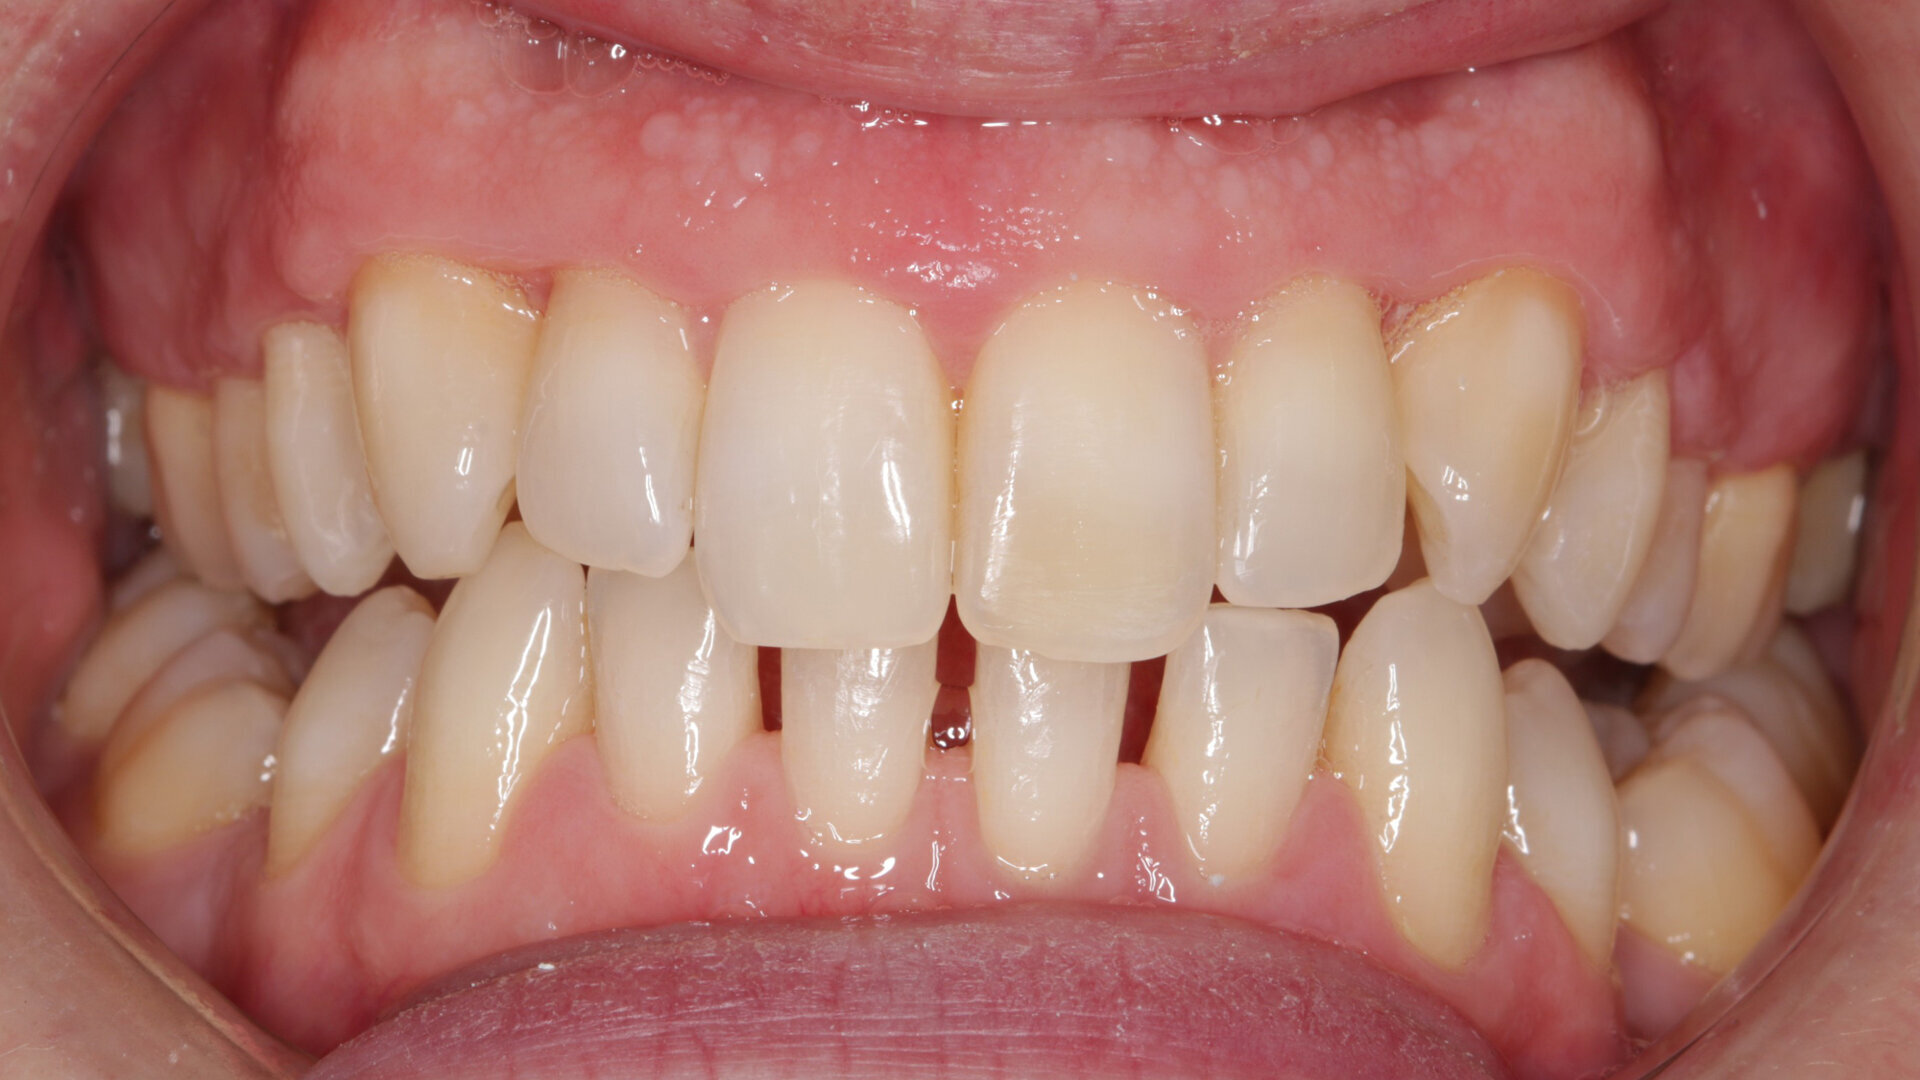

Fig. 2: Pre treatment smile

A 32-year-old male patient presented to our practice after he saw that we provide GDP orthodontics on our website. He came from an NHS practice and it was agreed that he would remain with that practice for his routine care. He was fit and well, took no medication, had no allergies and was a non-smoker. However, he was struggling with his oral hygiene and did not like the appearance of his maxillary teeth, specifically the colour and the alignment. He was not keen on the idea of fixed orthodontic appliances, but had heard about clear aligners.

My examination revealed nothing abnormal with his extra- or intra-oral soft tissue, temporomandibular joint or range of motion. However, his oral hygiene was poor, which was not helped by the crowding of his maxillary anterior segment. In addition, tooth #48 was carious. I carried out a full orthodontic assessment (Table 1) and took photographs.

I explained that the maxillary teeth could and should be aligned, as this would likely result in easier cleaning of the teeth, plus it would improve the appearance. The patient and I agreed that the mandibular teeth could remain untouched, as this would keep the cost down, but mainly because they did not bother him. The priority was to stabilise his periodontal condition. A basic periodontal examination Code 3 and heavy bleeding were recorded in each sextant. At that visit, I performed a gross scaling using the ultrasonic scaler and used a model to demonstrate both the use of flossettes and an oscillating toothbrush.